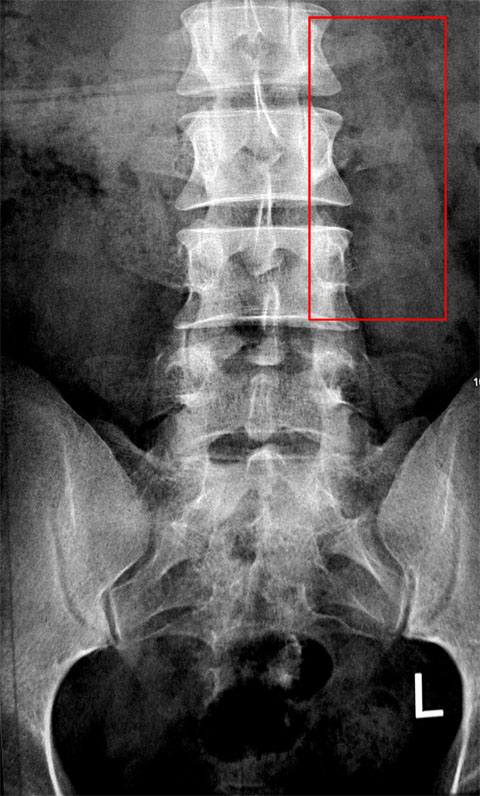

<P>从小到大,只有上小学3年级的时候把鼻梁骨摔过一次,身上其他地方一直没有骨折过,昨天让我终于打破了这个良好的纪录。。。。。。</P>

<P>比较郁闷的是居然是扑射在模式口大道上,较比不爽,主要是入弯速度过快,没有减速,要减速时,为时已晚。。。。。。。。。在瞬间把车踹出去,抱头,撞树,就让我得到了加入骨折帮的通行证了,幸亏是撞树了,要是当时急刹车,铁定侧滑,摔的肯定更惨 </P>

<P>PS: 馒头的骨盆很清楚 哈哈</P>